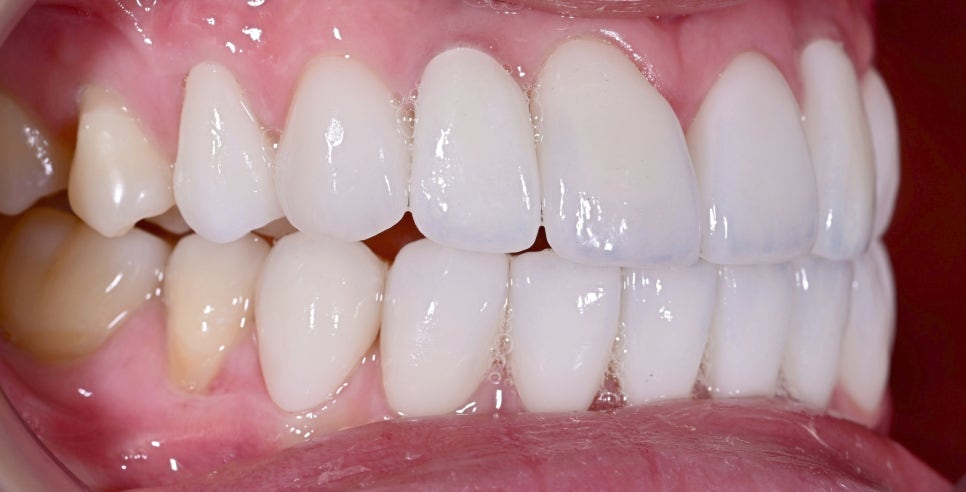

어떤 게 임플란트일까요?

라미네이트, 임플란트 시술 전

특히 기존 임플란트의 색감이나 모양, 위치감 때문에 어색해 보이는 경우에는 환자분들이 라미네이트를 고려하시는데, 라미네이트는 자연치아에만 시술할 수 있기 때문에 일부는 임플란트, 일부는 라미네이트로 시술해야 합니다.

여기서 중요한 점은 임플란트와 라미네이트의 생김새, 색이 동일해야 한다는 점입니다. 조금이라도 색이 다르거나 이질감이 들 경우 앞으로의 생활에서 매일같이 불편함을 느끼실 수도 있습니다.

환자분은 기존 앞니 임플란트가 주변 자연치와 잘 어우러지지 않아 웃을 때마다 어색한 느낌이 신경 쓰인다고 하셨습니다.

특히 임플란트는 식립해놓은 보철물이 내려가거나 잇몸과의 경계가 깔끔하게 들어맞지 않으면 티가 굉장히 많이 납니다.